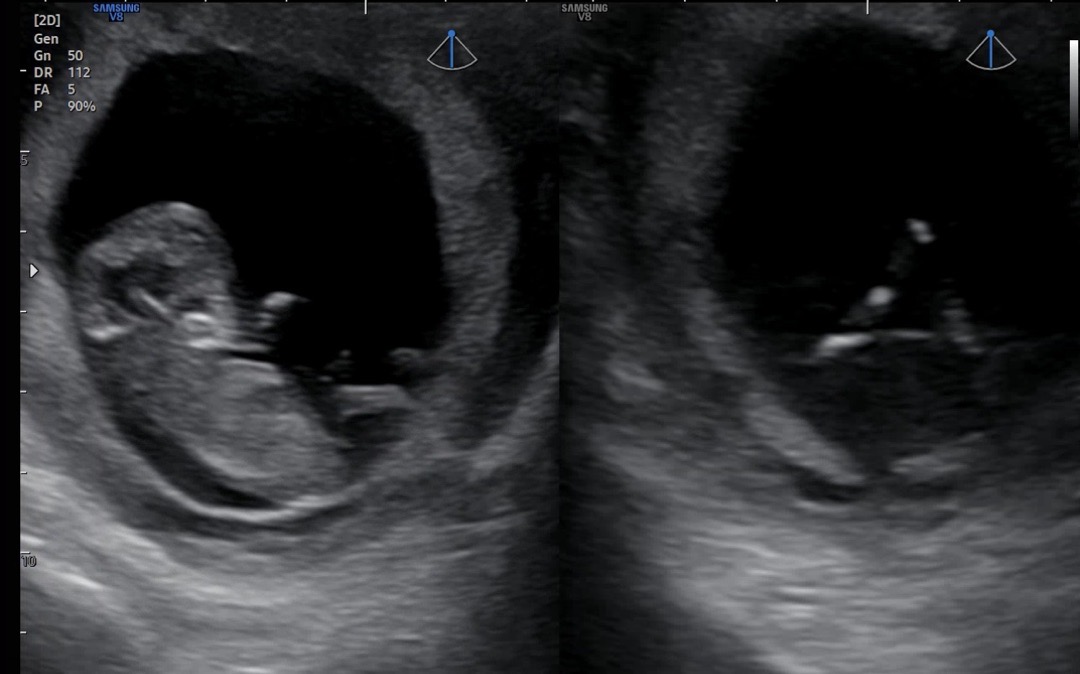

11주 3일차에도 성별을 알아볼수 있을까요?

오늘 목투명대 보러가서 다리쪽 5시방향의 🌶️존재감을 드러내는것이 보이는거 같아서요. 11주3일차인데 아들로 보이시는지 의견 부탁드려요👏